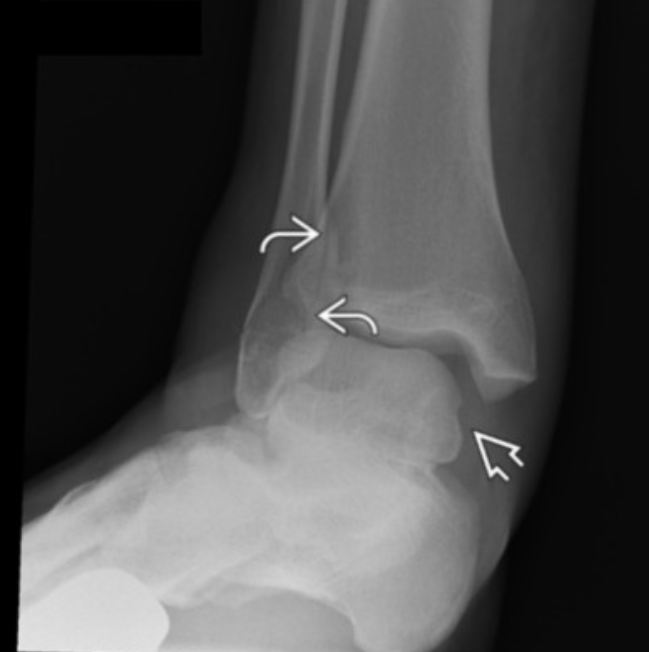

how do we know if this fracture is intraarticular in extension?

Boehler angle is reduced (normally 20-40, here is 10)

CT can confirm (sanders classification)